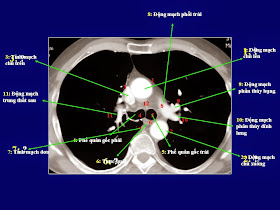

Chụp cắt lớp vi tính (CLVT) phổi và lồng ngực đánh giá được tình trạng bệnh lý của xương sườn, màng phổi, nhu mô phổi, phế quản, tim, mạch máu, trung thất…. Dựa vào hình ảnh chụp CLVT có thể nhìn thấy những bất thường mà không thể phát hiện dễ trên phim chụp X quang tiêu chuẩn thẳng hoặc nghiêng vì bị các tạng khác chồng lên che khuất.CT scanner là một phần của cắt lớp vi tính trong chẩn đoán hình ảnh. Để học được CT lồng ngực thì chúng ta cũng phải có những bước cơ bản trước. Đó là phải cần học giải phẫu trước. CT có độ phân giải cao hơn so với X quang thường quy, có độ chi tiết hơn vì vậy sẽ có nhiều chi tiết hơn. Đối với người bắt đầu học CT thì việc học giải phẫu sẽ khó khăn hơn chút. Để giúp ích cho việc học sau này tôi xin giới thiệu loạt slide bài giảng về giải phẫu lồng ngực. Bài giảng chỉ các mốc giải phẫu cơ bản lồng ngực qua các lát cắt. Hình ảnh minh họa dễ hiểu. Các bạn có thể bấm vào ảnh để xem ảnh phóng to để nhìn rõ các mốc giải phẫu như phân thùy phổi(thùy phải: 3 thùy; thùy trái:2 thùy), trung thất, xương.

| Click vào ảnh để phóng to |